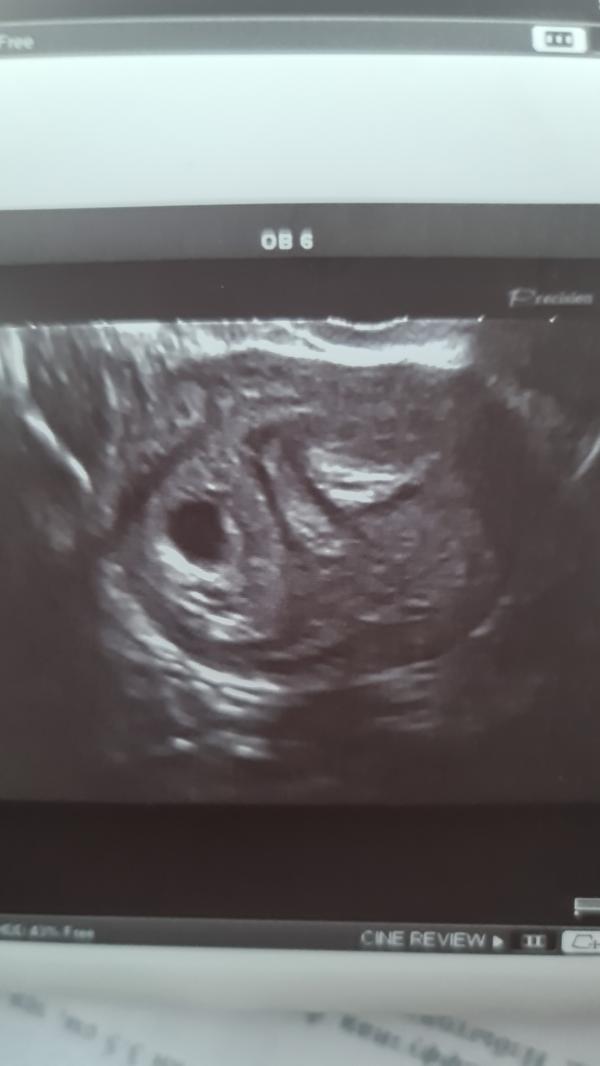

Я ложусь,он вставляет датчик с абсолютно спокойным настроем и тут он такой😱😱😱"Анастасия, вы что в себя поверили?вы как-то жёстко занимались сексом?африканские страсти?" И смеется сквозь шок и удивление во взгляде) мы начинаем ржать,я отшучиваюсь тоже,тут он зовет коллегу и медсестру и показывает картинку и говорит:"Вы знаете,то что я вижу не имеет ни медицинского,ни физиологического объяснения!я не знаю как это получилось,это можно считать чудом..или волшебством..". Ну и разворачивает экран ко мне и показывает, как матка разделилась ровно на 2 половины и в одной есть плодное яйцо,там эмбриончик и бьется сердечко(это уже видно,но не слышно),а с другой стороны грубейшие спайки и неоднородный эндометрий.В итоге он разрешил записать микро видео,где видно как качает сердечко и скзаал:"я сам тоже запишу видео,отправлю всем в институте,это просто капец ,я слов подобрать не могу и сейчас побегу к профессорам". Скзаал,чтоб я пришла через неделю еще раз,чтоб посмотреть как там развивается всё. ПО месячным было вчера 6.1 недель,а по плодному яйцу 5.5 недель,я думала что будет больше отставание,но нет,я рада))2 декабря увидимся снова.. и вот я опять переживаю,что же дальше будет с моей крошкой(((не помешает ли это всё развитию...слева плодное яйцо,а справа это все спайки,все эти неровности